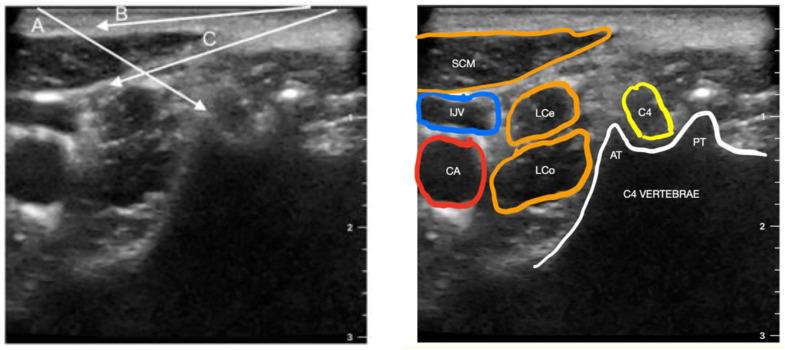

Postoperative pain is common following spine surgery, particularly complex procedures. The main anesthetic efforts are focused on applying multimodal analgesia beforehand, and regional anesthesia is a critical component of it. The purpose of this study is to examine the existing techniques for regional anesthesia in cervical spine surgery and to determine their effect and safety on pain reduction and postoperative patient's recovery. The electronic databases were searched for all literature pertaining to cervical nerve block procedures. The following peripheral, cervical nerve blocks were selected and described: paravertebral block, cervical plexus clock, paraspinal interfascial plane blocks such as multifidus cervicis, retrolaminar, inter-semispinal and interfacial, as well as erector spinae plane block and stellate ganglion block. Clinicians should choose more superficial techniques in the cervical region, as they have been shown to be comparably effective and less hazardous compared to paravertebral blocks.

脊柱手术后通常会出现术后疼痛,尤其是复杂的手术。主要的麻醉措施侧重于预先应用多模式镇痛,而区域麻醉是其中的关键组成部分。本研究旨在检查颈椎手术中现有的区域麻醉技术,并确定它们在减轻疼痛和术后患者恢复方面的效果和安全性。电子数据库中搜索了所有与颈椎神经阻滞程序相关的文献。选择并描述了以下外周和颈椎神经阻滞:椎旁阻滞、颈椎丛钟形阻滞、多裂肌颈、后层间、半棘间和筋膜间平面阻滞以及竖脊肌平面阻滞和星状神经节阻滞。临床医生应选择颈部较浅的技术,因为与椎旁阻滞相比,这些技术已被证明同样有效且危害较小。